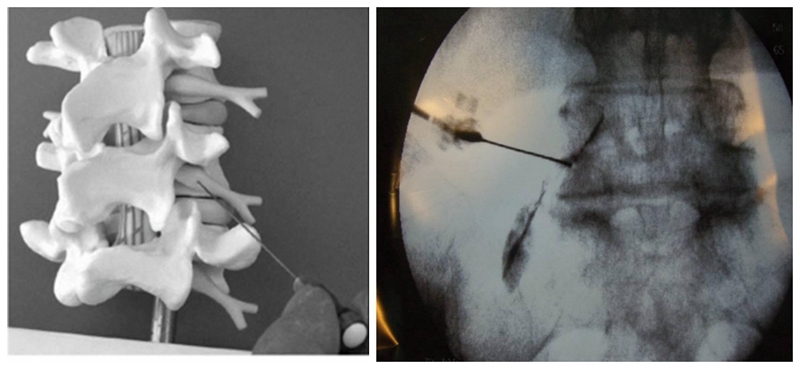

图1

腰椎经椎间孔注射术(Transforaminal injection)是利用穿刺针通过椎间孔进入神经根或硬膜囊的腹侧,进而注射药物,以达到诊断或治疗目的的一种方法,也是疼痛科医生或脊柱外科医生在腰椎疾病诊疗过程中常用的一种方式。

注射术有着悠久的历史,并经过不断的完善及演变。很早之前就有麻醉医师发现,经过骶裂孔注射局部麻醉药物后,患者的坐骨神经疼痛症状会得到明显缓解。1961年EN Coomes对比了经骶裂孔注射普鲁卡因和卧床休息治疗坐骨神经痛患者的临床效果,他认为,与卧床休息对比,经骶裂孔注射技术简单有效,患者采用俯卧位,10分钟即可完成,不需要住院治疗,这给人们治疗坐骨神经痛提供了一种新的治疗手段,但在当时EN Coomes仍认为这是一种“麻醉”技术。同年,在美国麻醉学家、疼痛治疗先驱之一Bonnica教授的倡导下,于美国华盛顿大学建立了第一所疼痛治疗中心,随后的1973年,国际疼痛学研究学会(IASP,international association for the study of pain)成立,一部分麻醉医生成为了疼痛科医生的先驱,并为治疗患者的各种疼痛症状而付出努力。